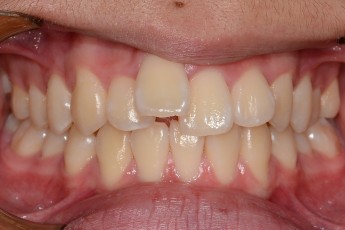

Before & After

- 덧니교정

Before

After